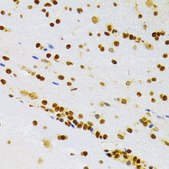

Anti-HMGB1 antibody produced in rabbit

immunohistochemistry

western blot

immunofluorescence: 1:50-1:200

immunohistochemistry: 1:50-1:200